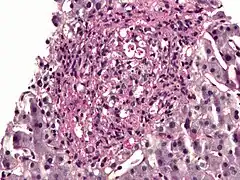

Histoplasma in a granuloma. PAS diastase stain.